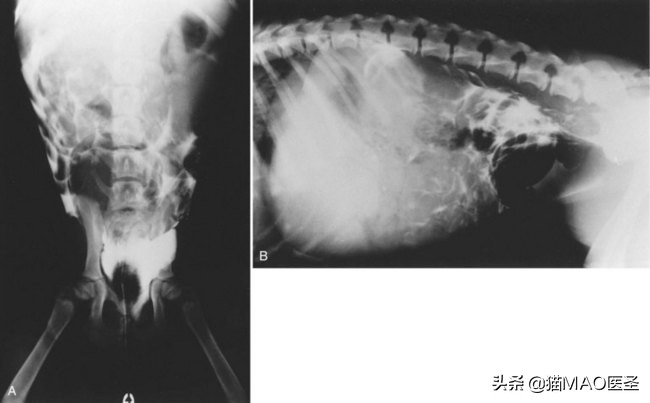

X射线。腹部x光检查以确定是否有液体存在于腹部或是否有任何肿瘤,肿块或肠阻塞。

B超。腹部超声可以用来确认腹水的存在,并帮助确定腹膜炎的潜在原因。腹部超声可以帮助检测肝脓肿,胰腺炎,肠阻塞或胆囊破裂。